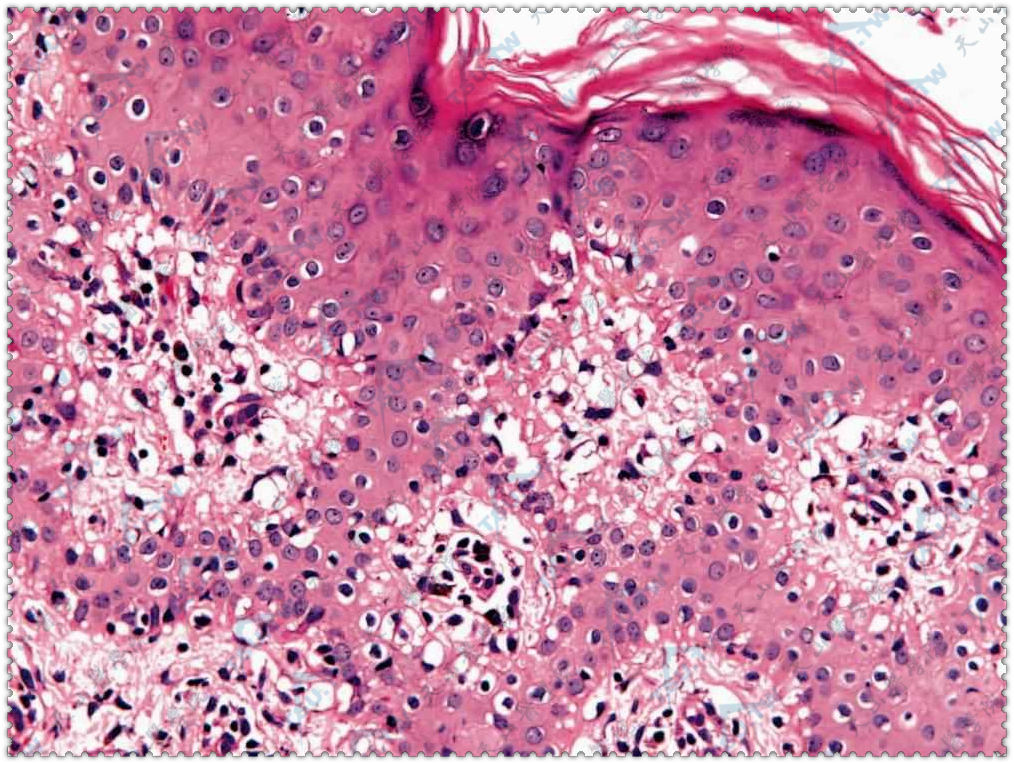

• 萎缩性慢性肢端皮炎

本病又名原发性弥漫性萎缩,主要发生于欧洲人中,美洲人中也有发病,我国极为罕见。女性发病率高于男性。病因本病是一种螺旋体病,为博氏螺旋体感染的晚期后遗症。Hauser等认为由硬